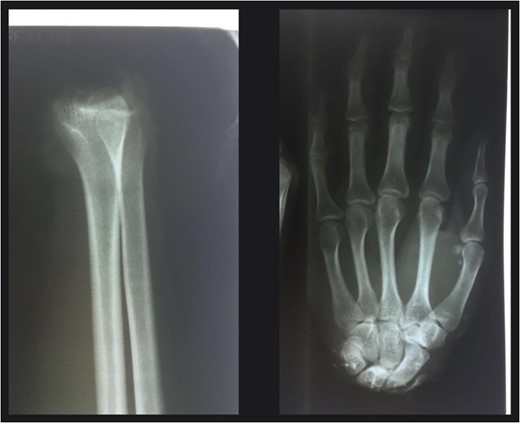

Monitoring every hour through pulse oximeter. First 48 h all indicators are above 95% in addition evaluation continues on capillary filling (always <2 s in all fingers), uniform temperature and similar coloring to that of the right hand. Evolution of patient was satisfactory, heparin was not used under molecular weight or derivatives, patient did not present immediate post-operative complications and was discharged from hospital 2 weeks after surgery.

Eight months after surgery he was taken into surgery to perform a tenolysis of the flexors. Patient attended physiotherapy at the hospital three times a week in a much disciplined manner for 14 months after surgery.